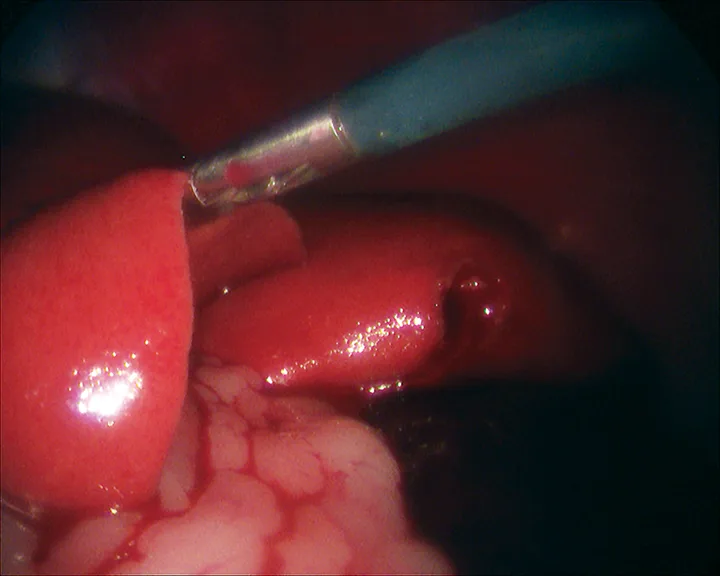

After placement of 2 ports and insufflation of the abdomen, the liver is examined and the lesion or lobe(s) to be sampled are identified. The lesion is grasped, then held in place for 15 seconds before the biopsy sample is removed (Figure 4). The biopsy site should be monitored for excessive bleeding. After adequate hemostasis is ensured, the port incisions are closed routinely. The lateral recumbency position prevents complete visualization of the dependent lobes; however, it does not preclude performing biopsies, if necessary.

FIGURE 4

Laparoscopic liver biopsy using a 5-mm cup biopsy instrument. A minor degree of hemorrhage from the previous biopsy site can be seen.